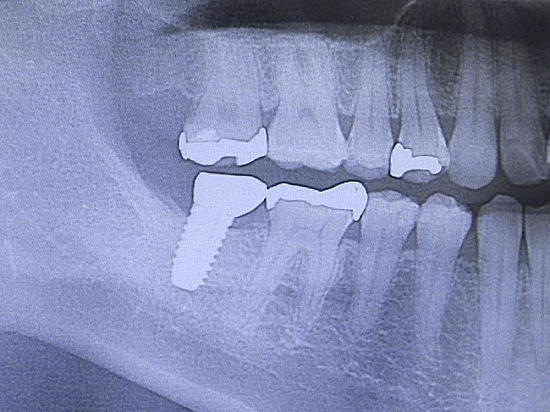

むし歯や歯周病などの病気や、事故で歯を失った患者様、先天的に歯が足りない方へお勧めしたいのが、インプラント(デンタルインプラント)治療。 インプラントとは、体内に埋め込む医療機器などの人工物や技術。例えば歯を1本失ってしまった場合、欠損部の両側の歯を削り、それを支えにして人工歯を被せる「ブリッジ」という治療が一般的です。ブリッジは支えとなる両側の健康な歯を傷つけてしまいます。そこで歯科治療の選択肢の一つとして、周囲の歯に影響の少ないインプラント治療をおすすめする場合があります。インプラントは、チタン製の人工歯根(フィクスチャー)を顎の骨に埋め込み、その上に土台(アバットメント)と人工の歯(上部構造)を合わせたものです。